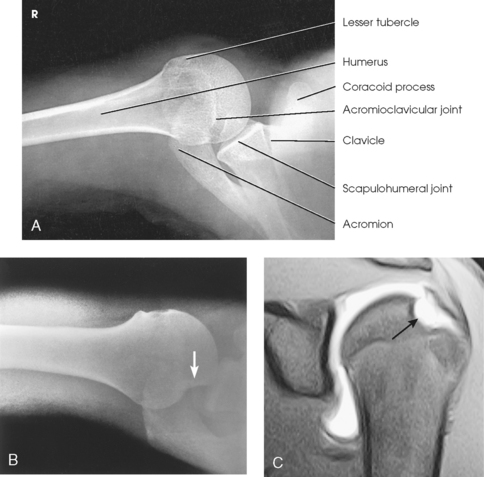

The proximal end of the humerus consists of a head, an anatomic neck, two prominent processes called the greater and lesser tubercles, and the surgical neck (Fig. 5-5). The head is large, smooth, and rounded, and it lies in an oblique plane on the superomedial side of the humerus. Just below the head, lying in the same oblique plane, is the narrow, constricted anatomic neck. The constriction of the body just below the tubercles is called the surgical neck, which is the site of many fractures.

Fig. 5-5 A, Anterior aspect of right proximal humerus. B, Photograph of anterior aspect of proximal humerus.

The lesser tubercle is situated on the anterior surface of the bone, immediately below the anatomic neck (Figs. 5-6 and 5-7; see Fig. 5-5). The tendon of the subscapular muscle inserts at the lesser tubercle. The greater tubercle is located on the lateral surface of the bone, just below the anatomic neck, and is separated from the lesser tubercle by a deep depression called the intertubercular (bicipital) groove. The superior surface of the greater tubercle slopes posteriorly at an angle of approximately 25 degrees and has three flattened impressions for muscle insertions. The anterior impression is the highest of the three and affords attachment to the tendon of the supraspinatus muscle. The middle impression is the point of insertion of the infraspinatus muscle. The tendon of the upper fibers of the teres minor muscle inserts at the posterior impression (the lower fibers insert into the body of the bone immediately below this point).

Fig. 5-7 Superior aspect of humerus. Horizontal section through scapulohumeral joint showing normal anatomic relationships.

The scapulohumeral articulation between the glenoid cavity and the head of the humerus forms a synovial ball-and-socket joint, allowing movement in all directions (Figs. 5-9 and 5-10). This joint is often referred to as the glenohumeral joint. Although many muscles connect with, support, and enter into the function of the shoulder joint, radiographers are chiefly concerned with the insertion points of the short rotator cuff muscles (Fig. 5-11). The insertion points of these muscles—the subscapular, supraspinatus, infraspinatus, and teres minor—have already been described.

Fig. 5-10 A, Coronal MRI of shoulder. Note articular cartilage around humeral head and muscles closely surrounding bone. B, Axial CT of shoulder, mid-joint. Note position of bones relative to each other and articular cartilage in glenoid cavity. gc, glenoid cavity; h, humerus; sn, scapular neck. (From Kelley LL, Petersen CM: Sectional anatomy for imaging professionals, ed 2, St Louis, 2007, Mosby.)

Structures shown: The image shows the bony and soft structures of the shoulder and proximal humerus in the anatomic position (Figs. 5-14 to 5-16). The scapulohumeral joint relationship is seen.